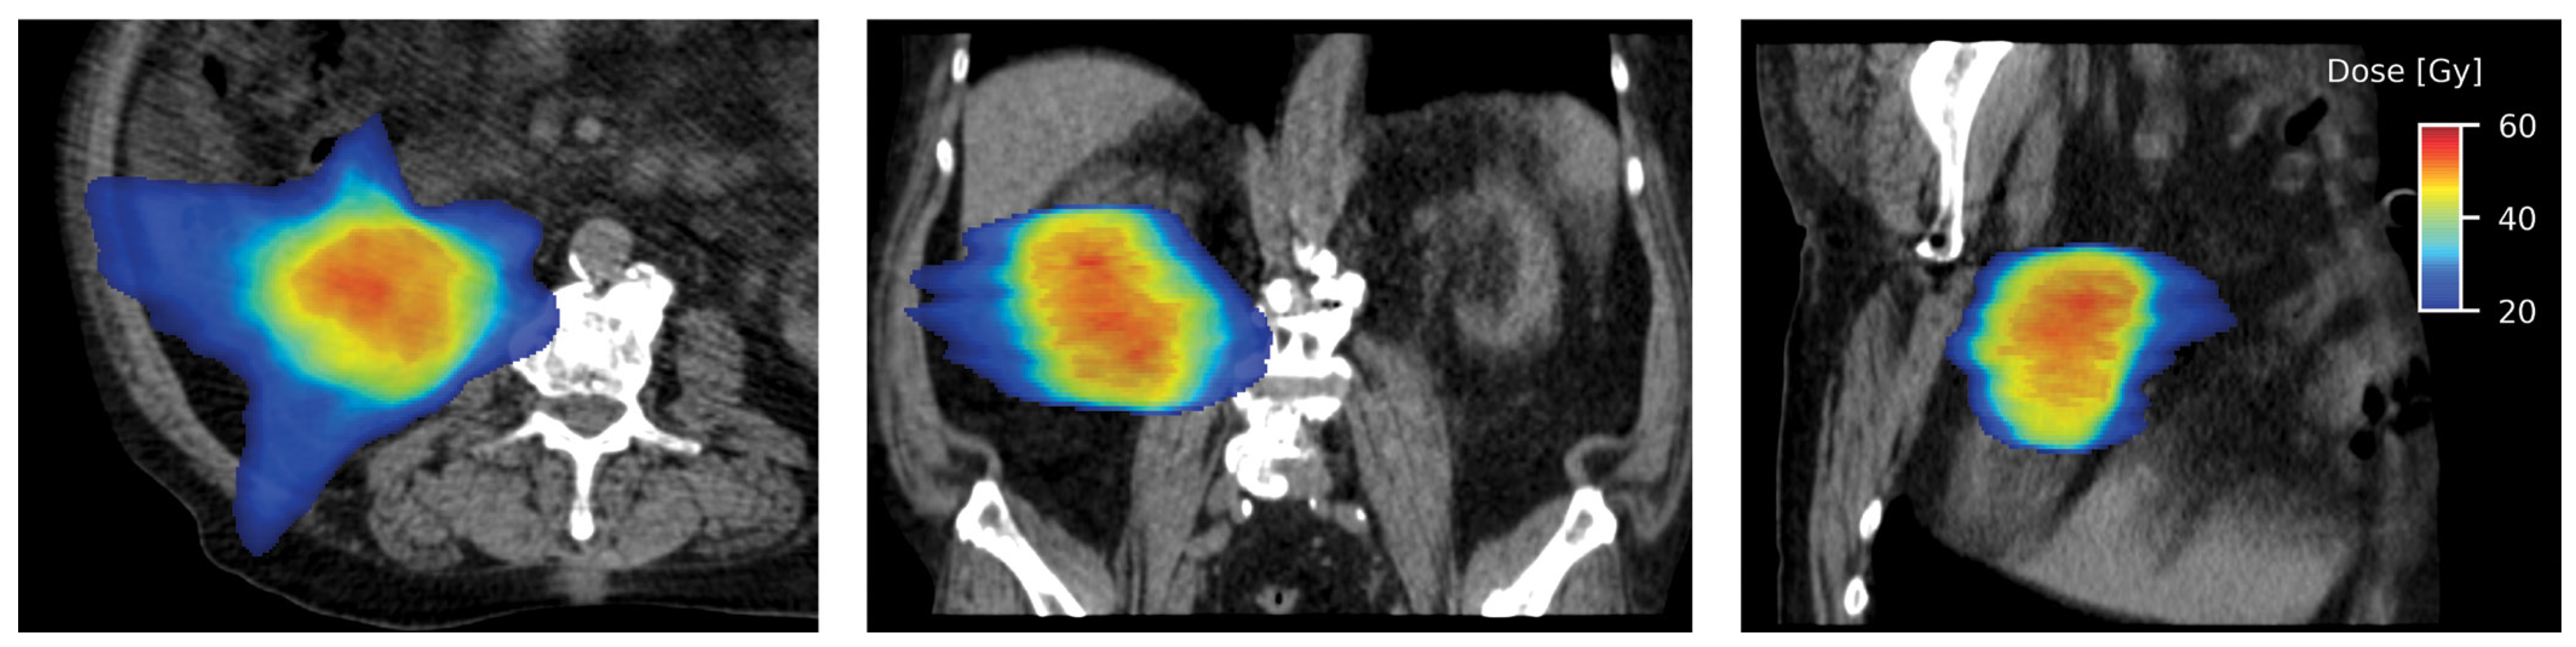

Technical Consideration

Clinical Evidence for SABR in Localized Primary RCC